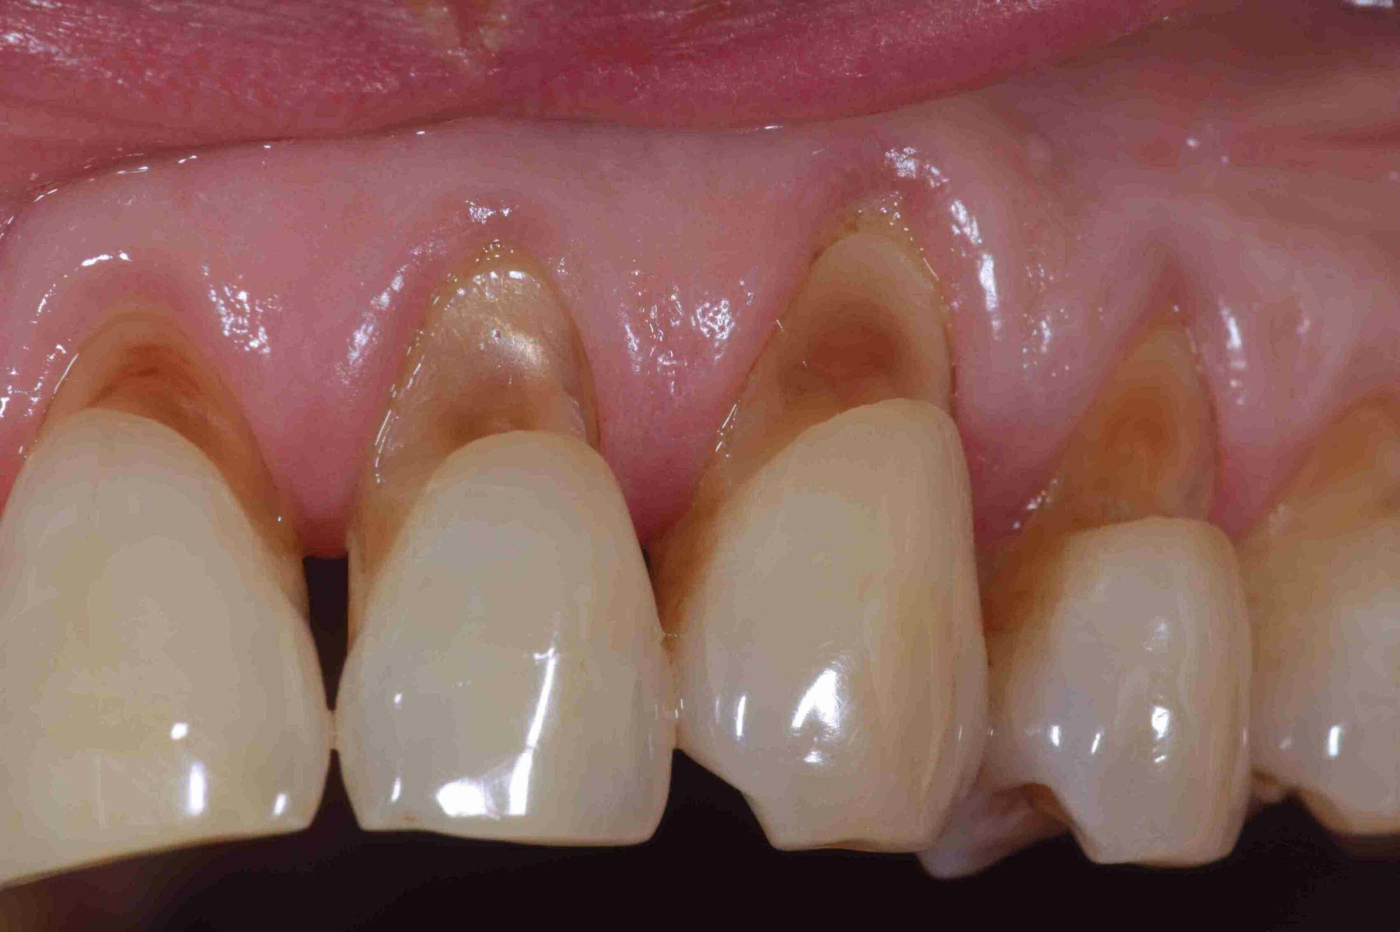

Mengutip laman Online Dental Programs, abrasi biasanya terjadi di area gigi yang dekat dengan gusi, bukan di permukaan atas gigi.

Masalah ini lebih sering terjadi pada gigi geraham depan (premolar) serta gigi taring.

Gigi yang terkikis biasanya akan berwarna lebih kuning dan mengilat dibandingkan gigi lainnya. Gigi tersebut biasanya membentuk pola menyerupai huruf V.

Selain itu, abrasi bisa membuat gigi jadi lebih sensitif. Pasalnya, abrasi yang mengikis lapisan enamel akan membuat lapisan di bawahnya lebih mudah menerima rangsangan dari makanan atau minuman.

Gigi biasanya terasa ngilu ketika Anda mengonsumsi makanan yang terlalu panas, dingin, atau asam.

Jika dibiarkan, abrasi gigi bisa mengikis lapisan yang lebih dalam dan menimbulkan masalah gigi yang lebih parah, seperti gigi berlubang dan penyakit gusi.